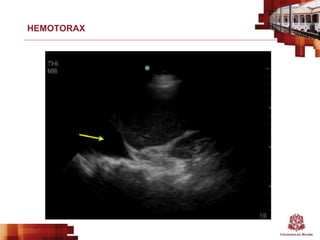

HEMOTORAX